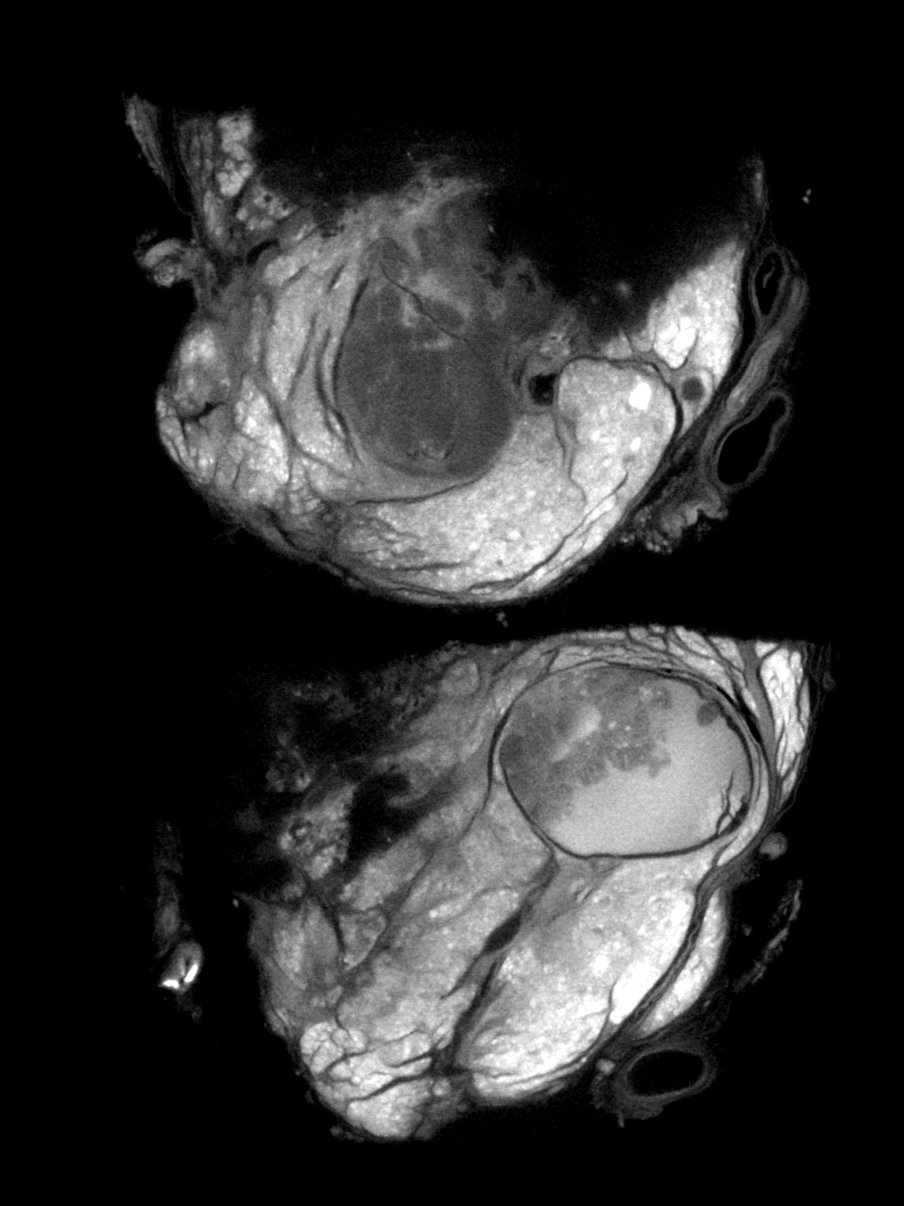

Imaging always involves a trade-off: higher resolution images mean more noise, and longer scans aren’t always practical. DeepDeblur3D is a deep learning model that breaks this trade-off by simultaneously denoising and sharpening 3D micro-CT volumes in a single pass.

A key feature is the inference-time control mechanism, which lets users independently tune the denoising and sharpening strength without retraining. This makes it easy to adapt to different scan qualities and analysis goals.